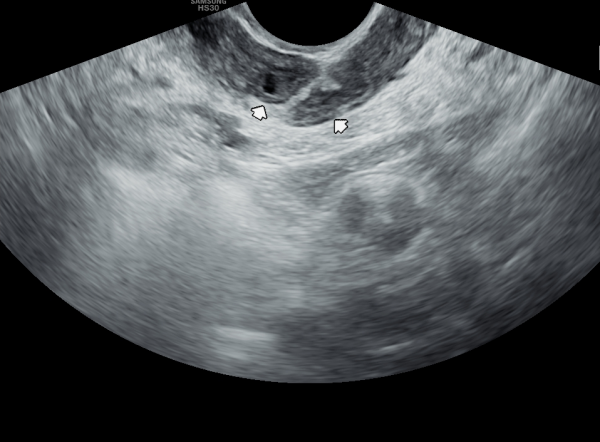

내원 첫날 정면 경직장 전립선 초음파 정낭의 검사상 사정관 입구의 순환 장애로 정낭의 낭종이 관찰되는 초음파 사진입니다.

This is a transrectal prostate ultrasound image taken on the first visit, showing a cyst in the seminal vesicle caused by a circulation blockage at the entrance of the ejaculatory duct.